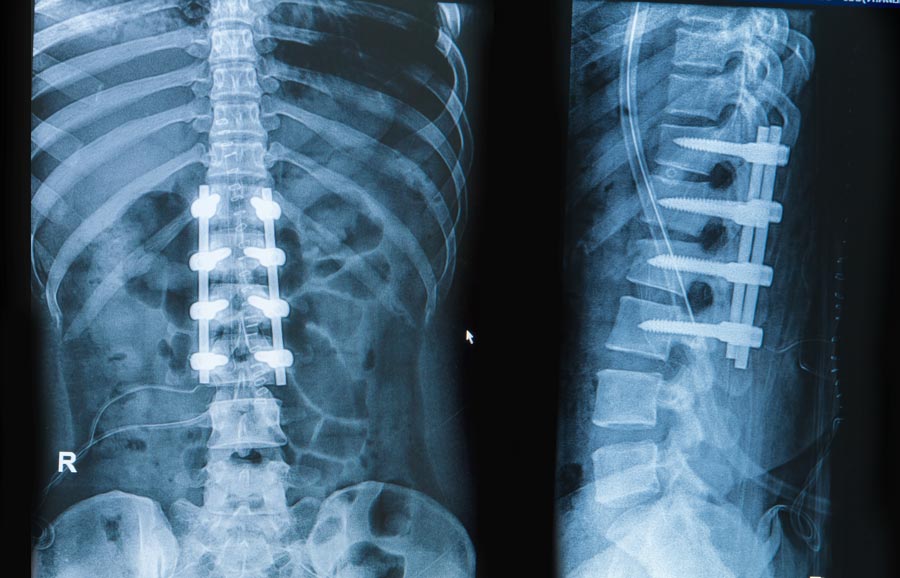

- Upon placing the bone graft between the vertebrae, the surgeon may place screws, plates or rods to hold the spine still. Finally, once the procedure is done the surgeon will close the incision with stitches or staples.